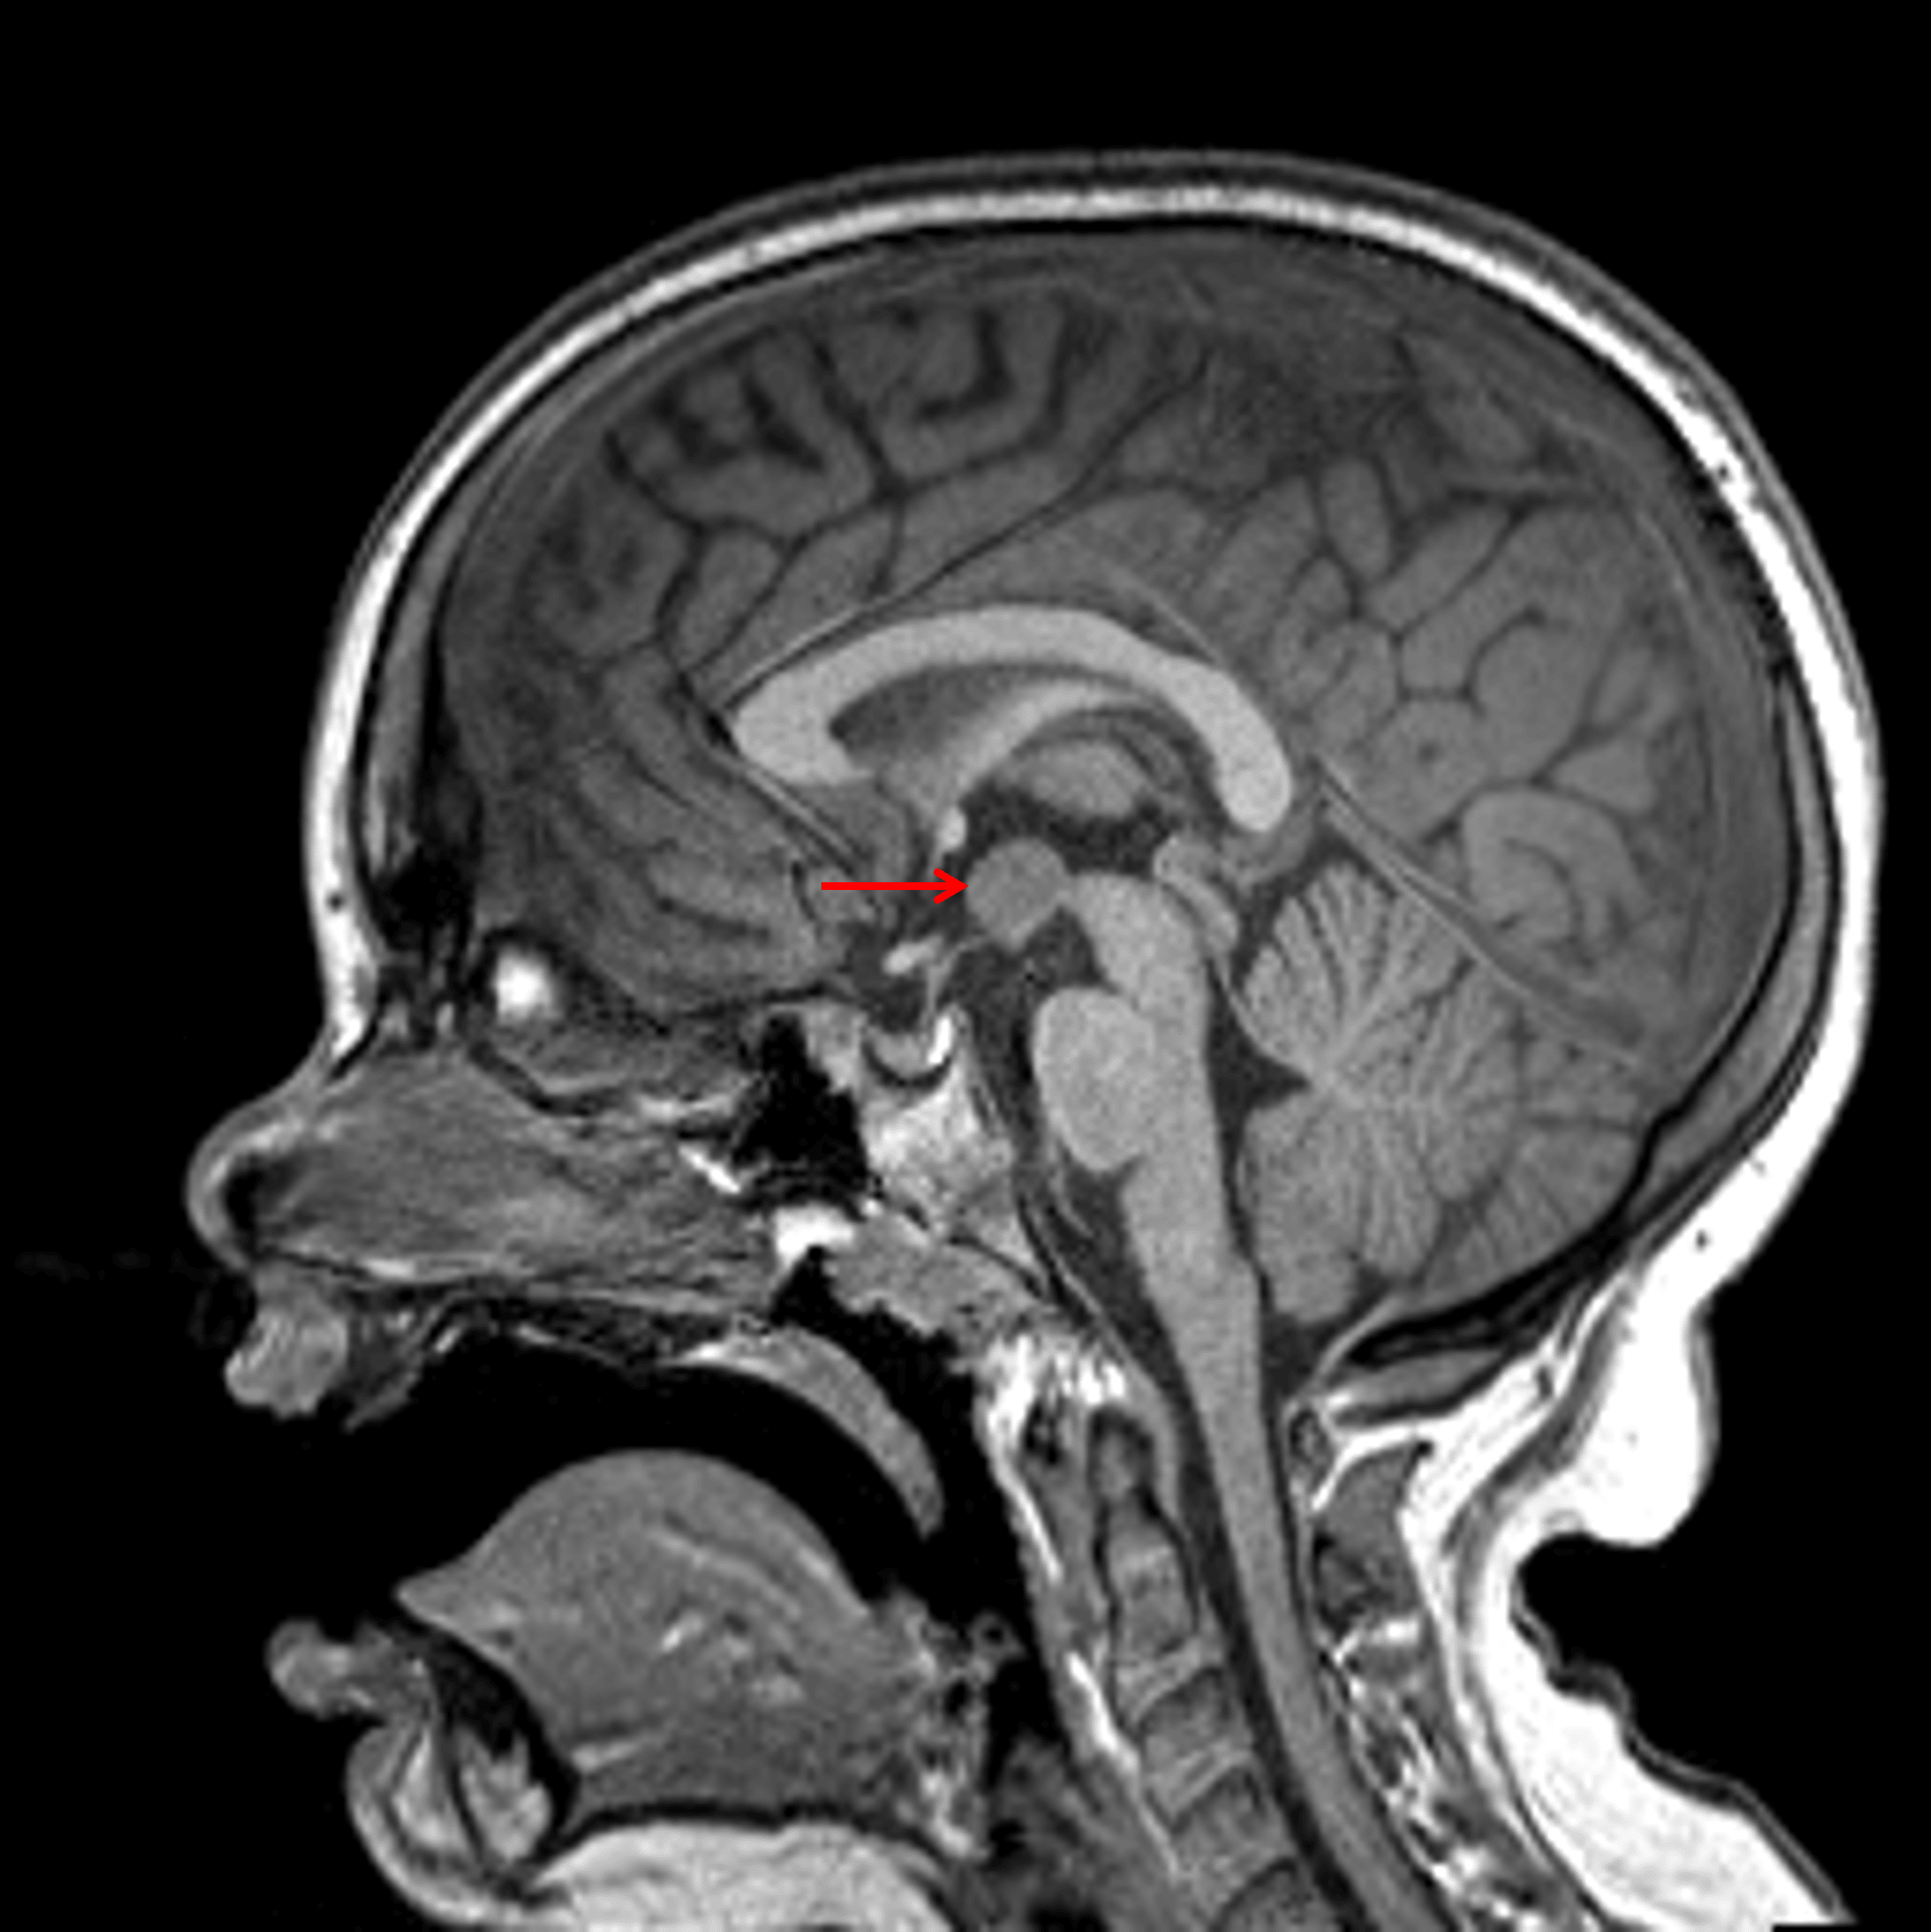

- Nonenhancing mass in the right eccentric floor of the third ventricle (tuber cinereum) measuring 12 x 10 x 9 mm, which follows gray matter signal on all sequences

- Mild mass effect on the right lateral wall of the third ventricle, the right mammillary body, and the right forniceal column

- No herniation or hydrocephalus

Rounded mass centered on the floor of the third ventricle which is isointense to gray matter (red arrow), consistent with a hypothalamic hamartoma.